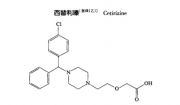

| 2021年7月26日 (一) 20:03 | 西替利嗪结构式.jpg (文件) |  |

11 KB | Uploaded with SimpleBatchUpload | 3 |